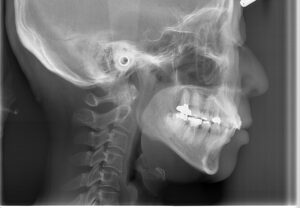

上顎の外科的骨切り術

上顎の前方への過成長が原因の場合、顎そのものを一部切除して後ろに下げます。顎を後ろに下げますから根本的な改善が可能です。矯正治療で、抜歯をして治療することがあります。犬歯の1本後ろの歯を抜歯することが多いのですが、その歯と骨を切除するというイメージです。自費治療で全身麻酔下での手術となります。また噛み合わせに問題がなければ、上が後ろに下がった分、下顎も下げないといけません。上だけがいわゆる出っ歯であれば上だけで済むこともあります。